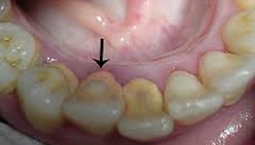

Os pacientes que que estão fazerdo ortodontia, precisam constantemente de cuidados, pois a dificuldade de higenização e da autoclise, facilita o aparecimento de problemas periodontais. Observa-se que no incisivo superior esquerdo, nete paciente, existe um abscesso no ápice, indicando um sério problema perio – endodôntico. Além do mais, deve-se considerar que durante a movimentação dos dentes está havendo, atividade osteoclástica (reabsorção óssea) e osteoblástica (formação óssea). Este equilíbrio biológico pode ser alterado se houver, algum processo inflamatório, e consequentemente reações imunológicas na área.